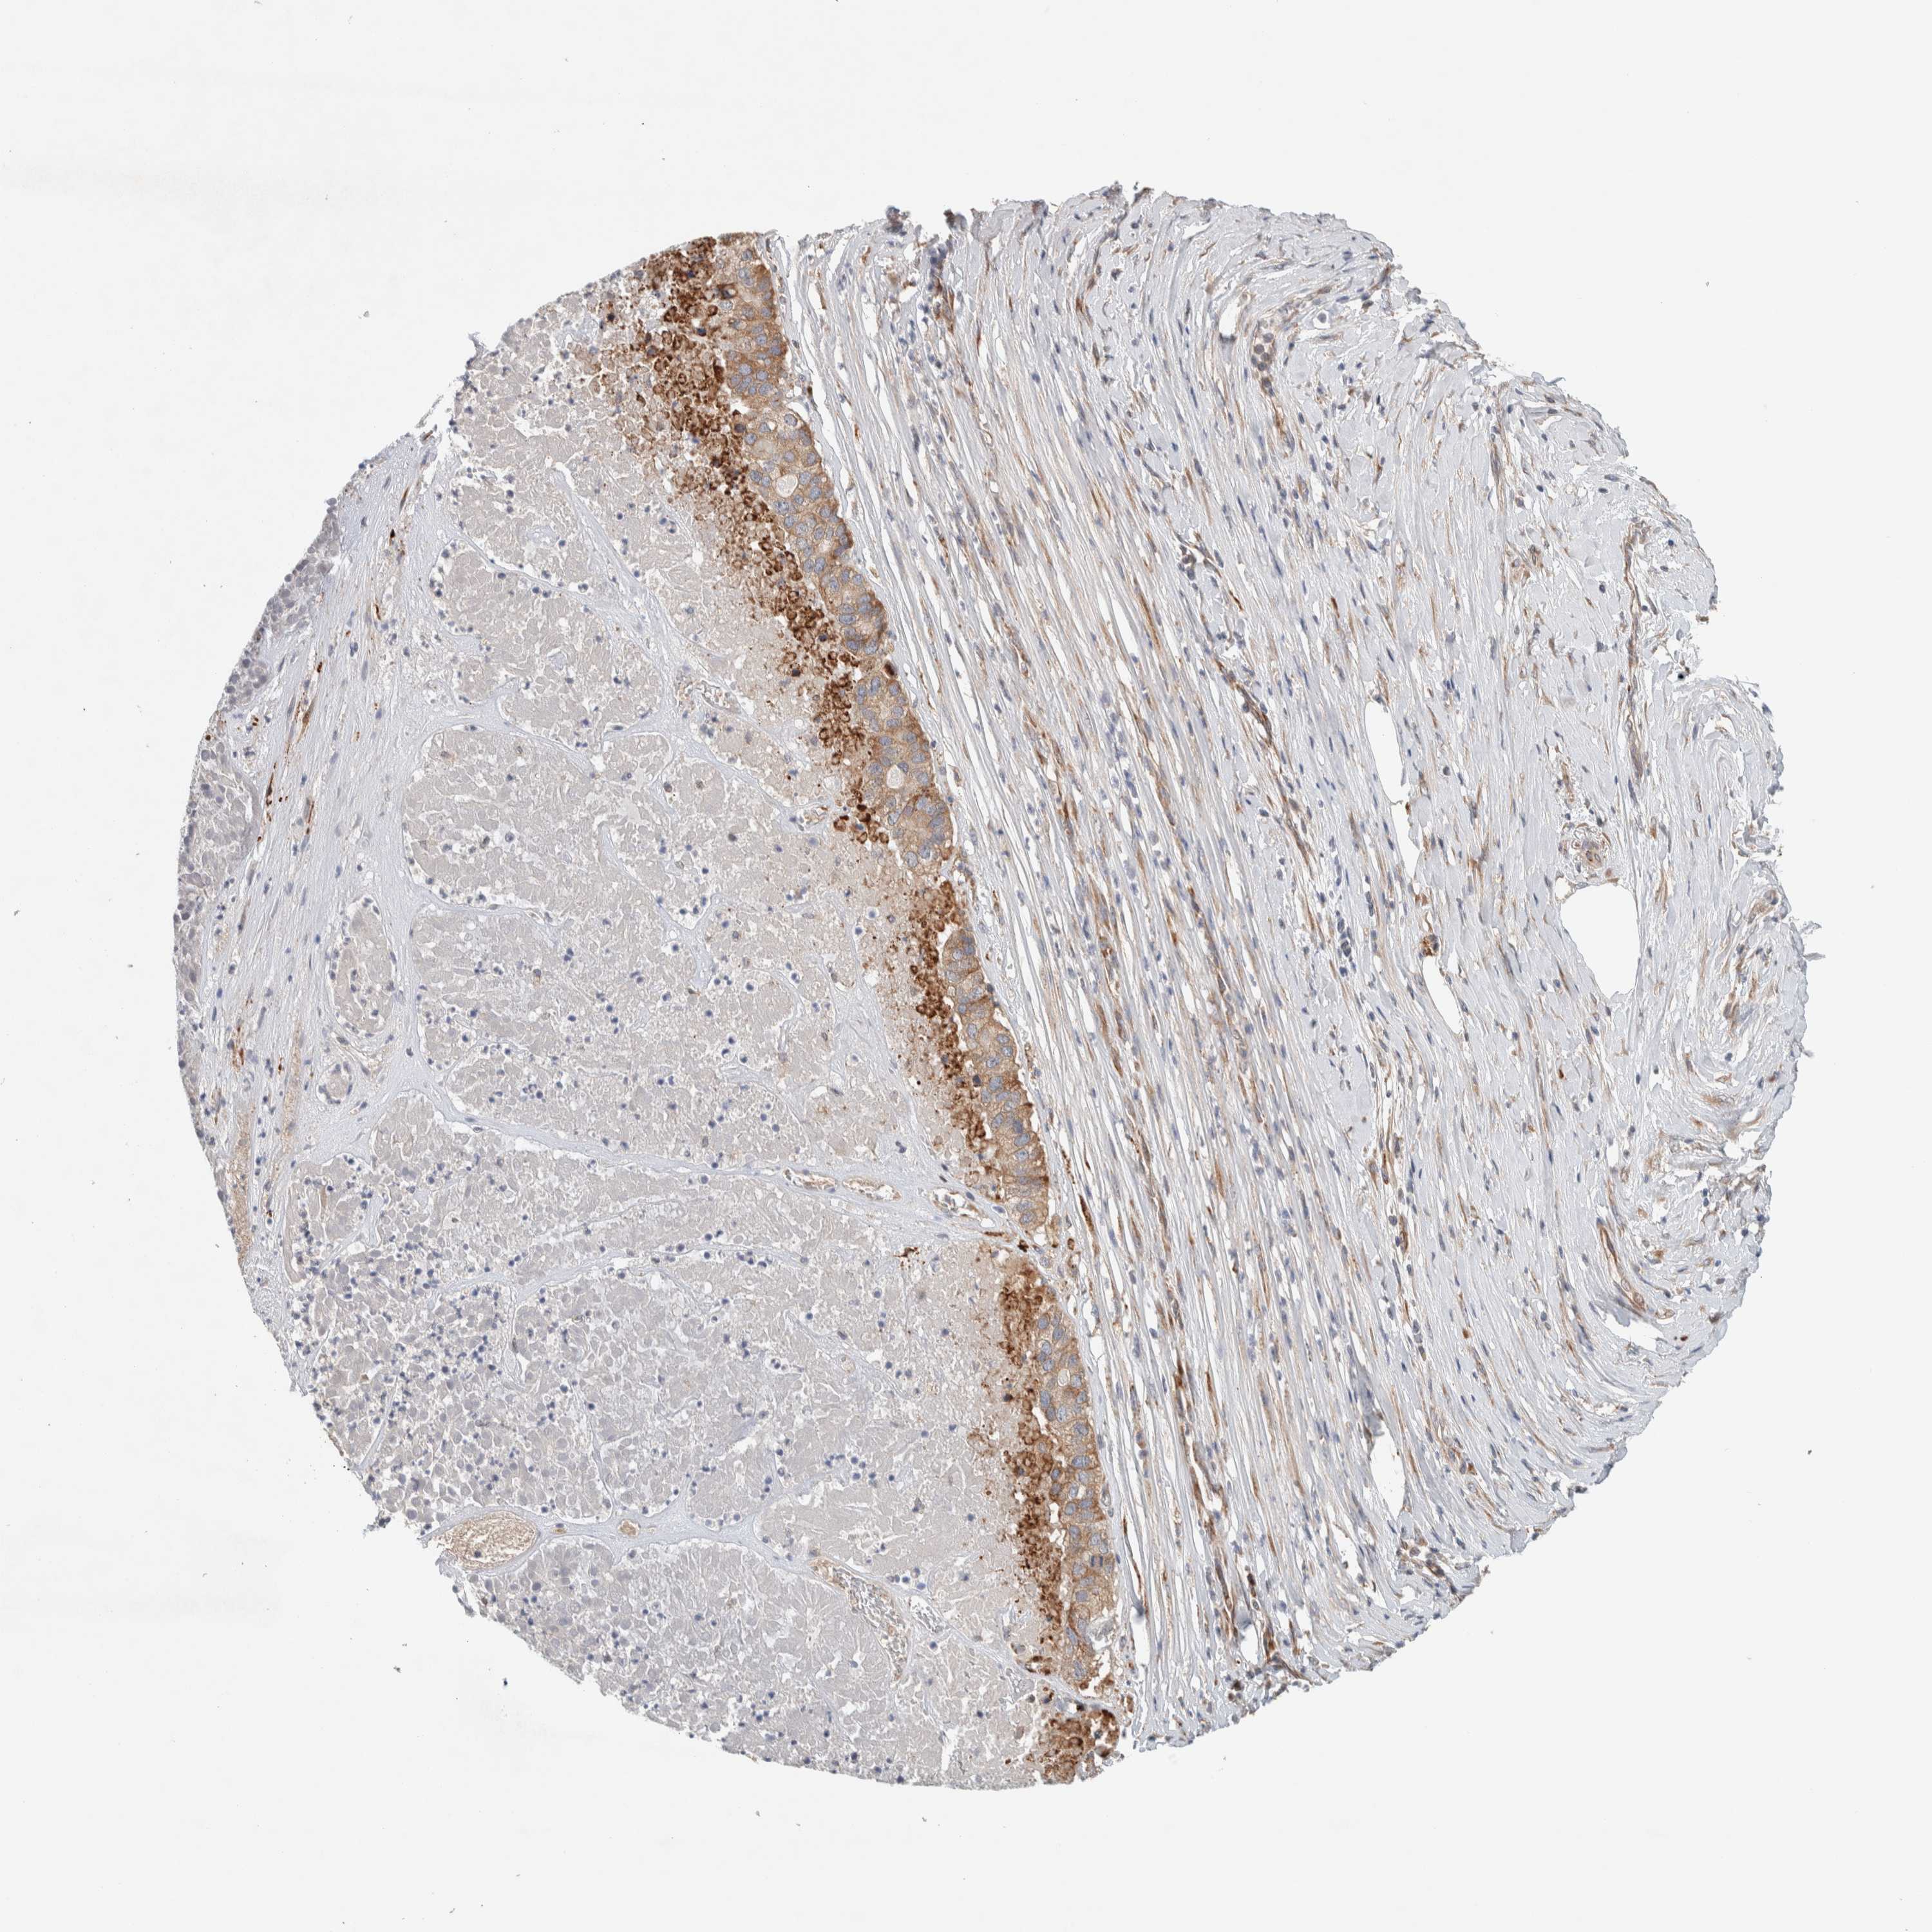

PANCREATIC CANCER - Protein expressioni

A mouse-over function shows sample information and annotation data. Click on an image to view it in a full screen mode. Samples can be filtered based on level of antibody staining by selecting one or several of the following categories: high, medium, low and not detected. The assay and annotation is described here.

Note that samples used for immunohistochemistry by the Human Protein Atlas do not correspond to samples in the TCGA dataset.

Antibody stainingi

Antibody staining in the annotated cell types in the current human tissue is reported as not detected, low, medium, or high, based on conventional immunohistochemistry profiling in selected tissues. This score is based on the combination of the staining intensity and fraction of stained cells.

Each image is clickable and will lead to virtual microscopy that enables deeper exploration of all samples and also displays staining intensity scores, fraction scores and subcellular localization as well as patient and tissue information for each sample.

Antibody HPA024291

Antibody CAB018652

Staining

High

Medium

Low

Not detected

Intensity

Strong

Moderate

Weak

Negative

Quantity

>75%

75%-25%

<25%

None

Location

Nuclear

Cytoplasmic/membranous

Cytoplasmic/membranous,nuclear

Adenocarcinoma, NOS